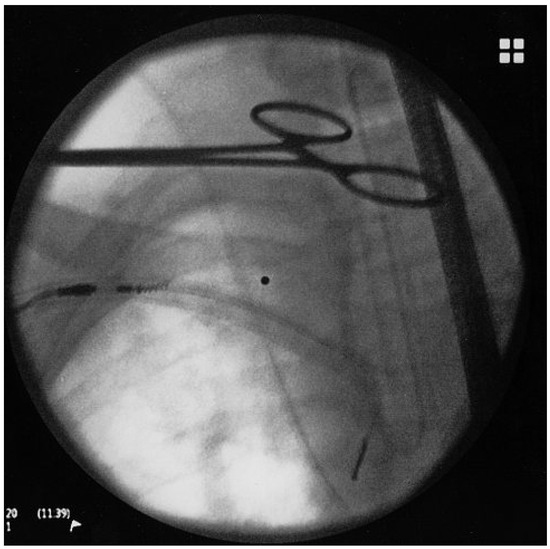

Use of Double Wire Traction for Removal of Pacemaker Leads

by Christine Arnold, Joanna Tenkorang, Juerg Schlaepfer and Martin Fromer

Cardiovasc. Med. 2011, 14(6), 189; https://doi.org/10.4414/cvm.2011.01599 - 29 Jun 2011

Retraction of device leads may be a risky procedure. We report a case of a patient with a pacemaker pocket infection and two abandoned leads. Locking stylets were introduced in each electrode and both stylets were pulled through the rotating blade with simultaneous [...] Read more.

Retraction of device leads may be a risky procedure. We report a case of a patient with a pacemaker pocket infection and two abandoned leads. Locking stylets were introduced in each electrode and both stylets were pulled through the rotating blade with simultaneous retraction and rotation of the blade. This technique allowed successful liberation of both leads at once. Full article